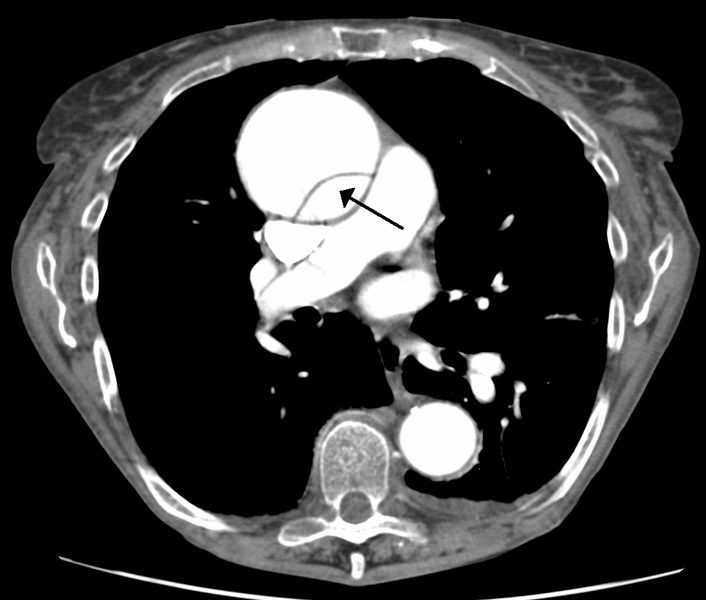

CT chest with contrast of thoracic aortic dissection.

| current | 17:45, 19 May 2016 | 1,030 × 875 (352 KB) | Alvarez13 (talk | contribs) | CT chest with contrast of thoracic aortic dissection. |